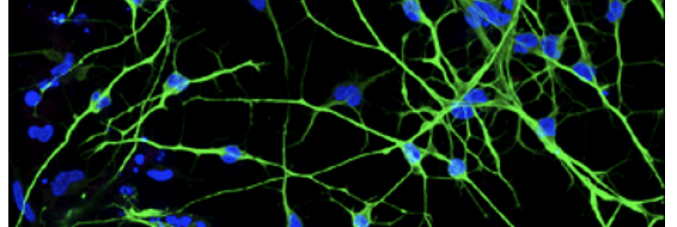

A research team from the University of Padua and the Veneto Institute of Molecular Medicine (VIMM), led by Onelia Gagliano and Cecilia Laterza, has developed an innovative method to generate human neurons more rapidly, efficiently, and cost-effectively than traditional techniques. The study, EEarly Reprogramming Intermediates Enable Direct Neuronal Conversion Via NGN2, published in the Journal of Molecular Neuroscience, shows that it is possible to obtain neurons from patients’ skin cells in just 12 days, compared to the 6–8 weeks required by conventional methods.

The new strategy is based on a short phase of partial reprogramming lasting about 3 days, followed by 9 days of neuronal induction, avoiding the full transition through a pluripotent stem cell state. The researchers identified a “time window” of high cellular plasticity, in which cells—no longer fibroblasts but not yet stem cells—are particularly responsive to signals that guide their transformation into neurons. In this phase, activating a single key gene, NGN2, is sufficient to effectively direct the conversion.

This approach addresses a crucial challenge in neuroscience research: the inability to directly study patients’ neurons. Generating neurons in the lab makes it possible to analyze diseases such as Alzheimer’s, Parkinson’s, and ALS in human cells, improving the understanding of disease mechanisms and making drug testing more reliable than with animal models. Moreover, compared to existing techniques, the new method reduces time, costs, and risks related to residual stem cells, while also improving overall efficiency.

The potential applications are broad and include studying neurological diseases, large-scale drug screening, and developing personalized medicine approaches. Future research will focus on verifying the full functional maturity of the generated neurons, further investigating cellular plasticity mechanisms, and applying the protocol to patient-derived cells to validate its effectiveness in real disease models.